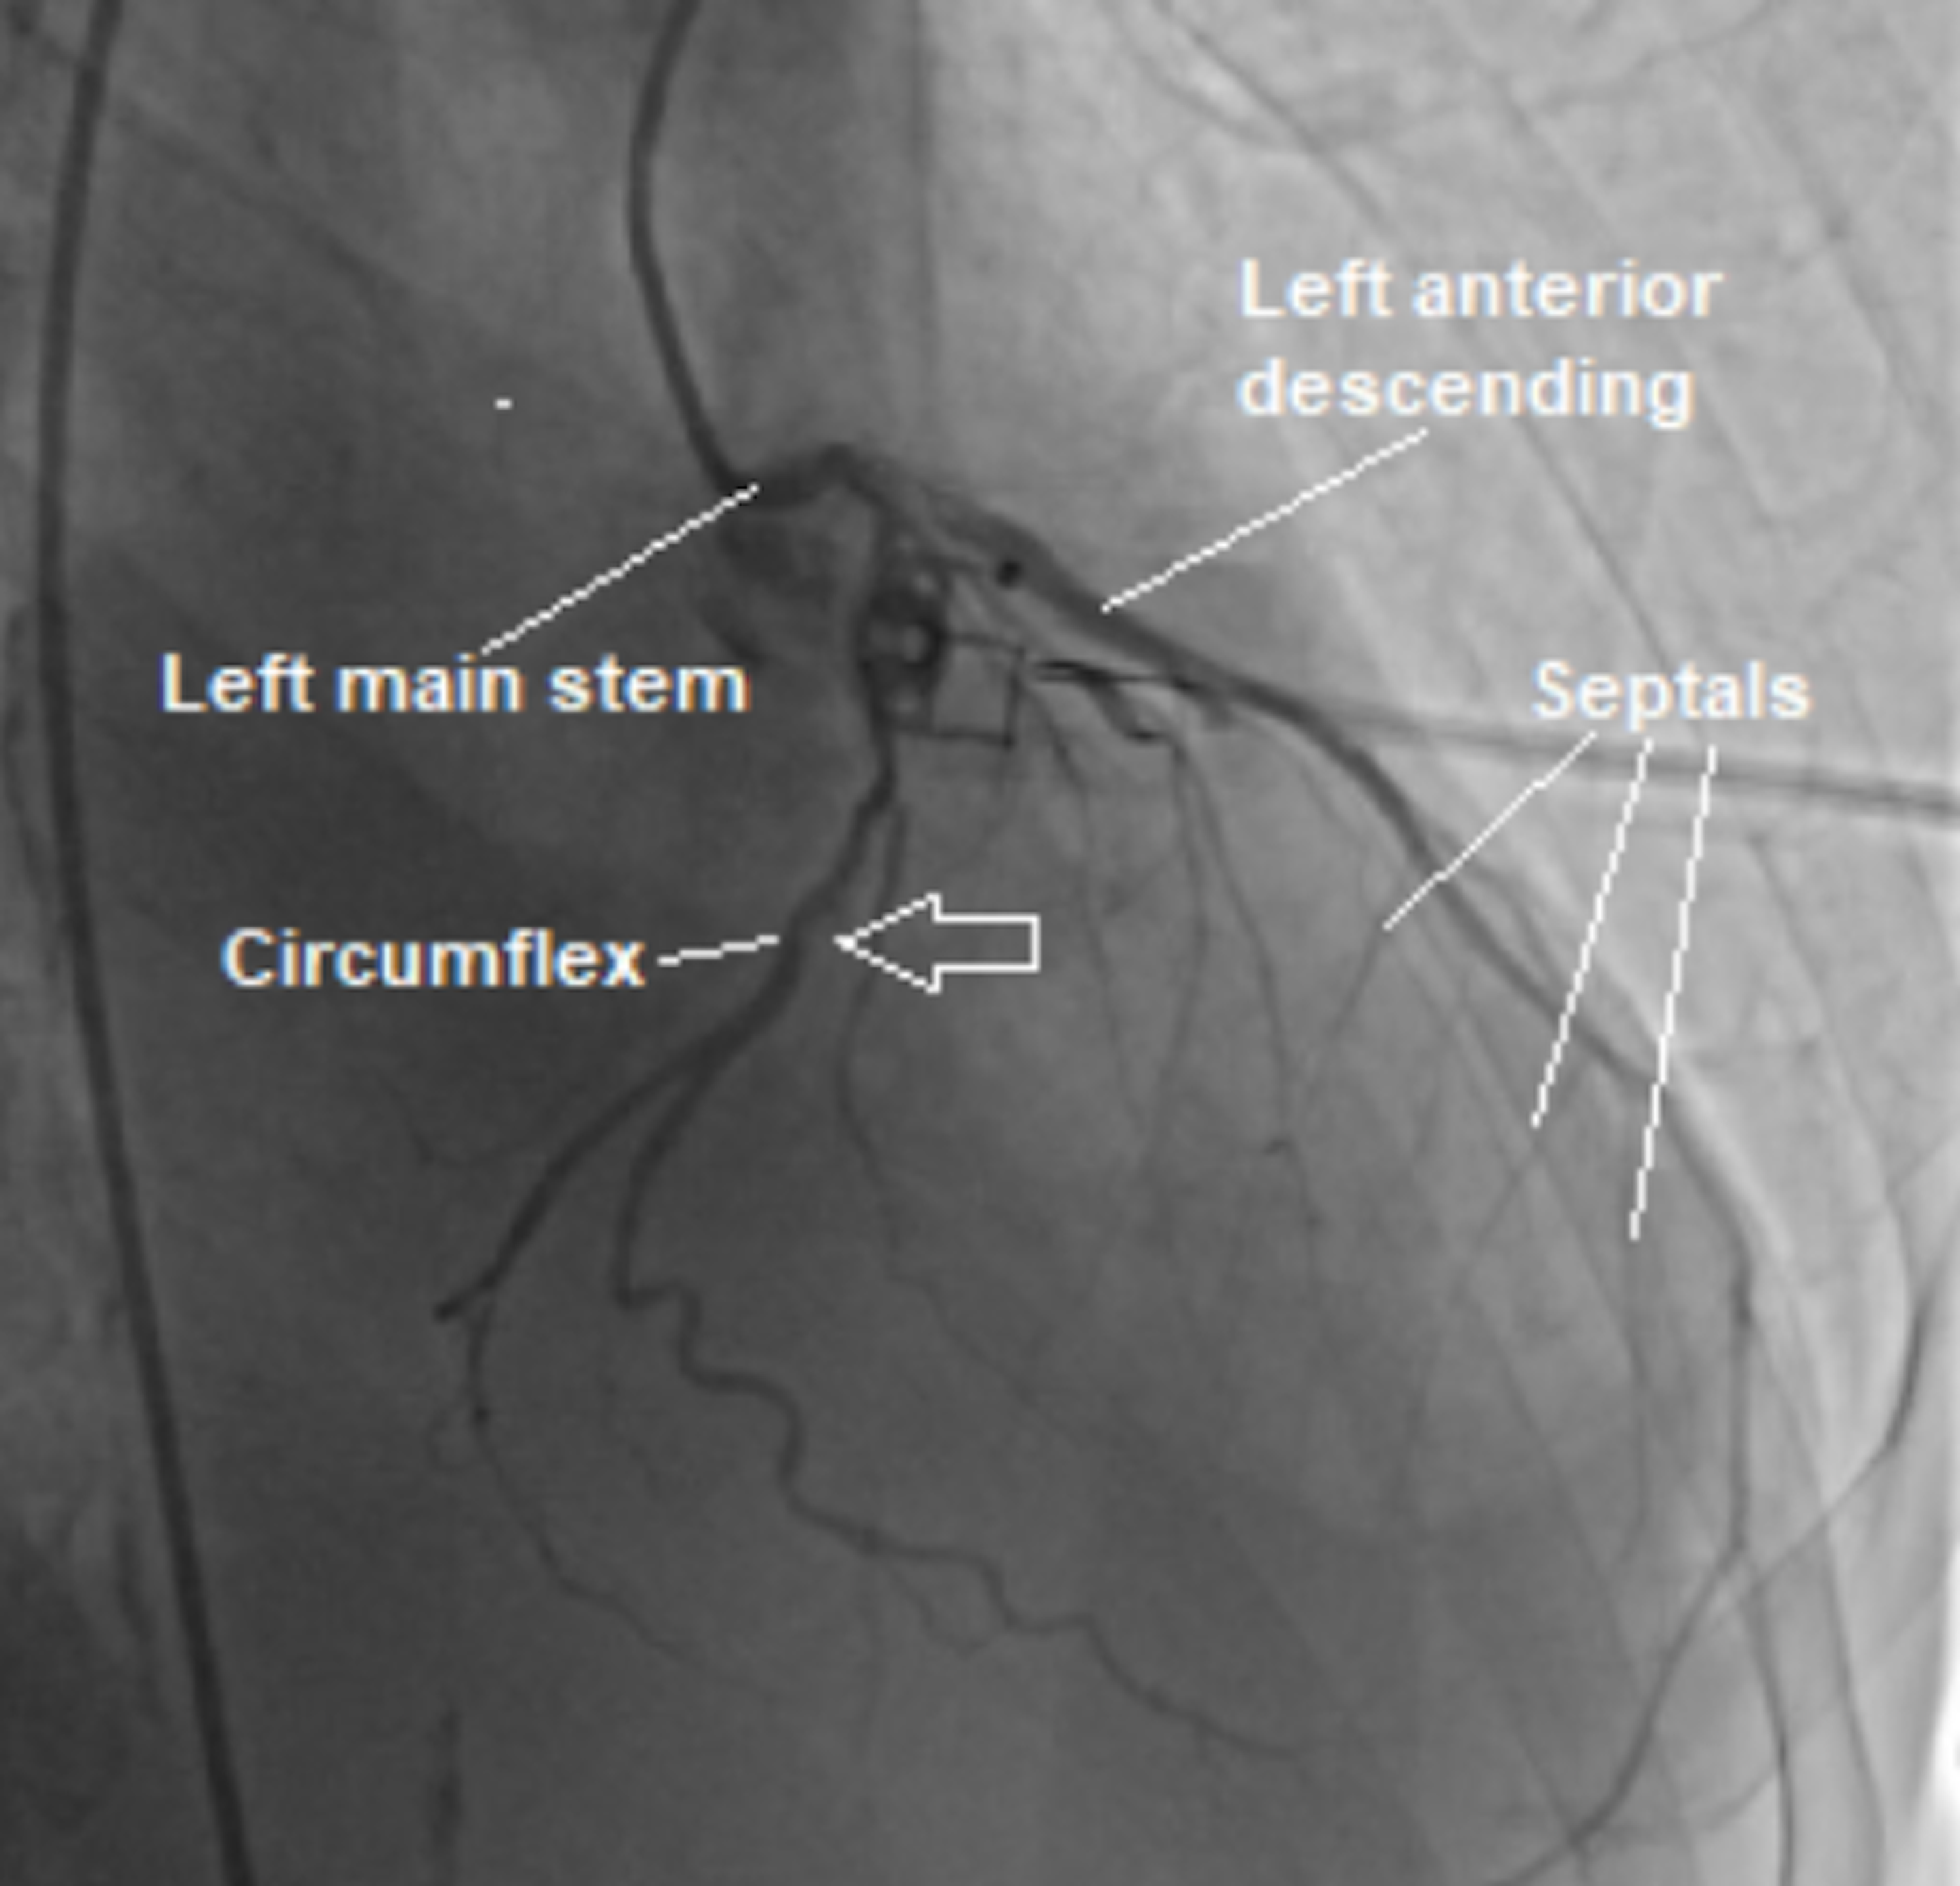

Figure 2 from A Large Isolated Congenital Left Circumflex Artery-to …

Isolated hypoplastic circumflex coronary artery: a rare cause of …

Corornary angiogram showing dilated circumflex artery and coronary …

Isolated Disease of the Ostium Left Anterior Descending or Circumflex …

Coronary angiogram: showing left circumflex coronary arteries tumor …

Anomalous origin of left circumflex artery from the right pulmonary …

Right Coronary Artery and Left Circumflex Artery Stent Placements …

Isolated Disease of the Ostium Left Anterior Descending or Circumflex …

-A) 70%-obstructive lesion of the proximal 1/3 of the circumflex …

Computed tomography. Huge left circumflex artery to right atrium …

Exercise myocardial nuclear perfusion scan shows basal lateral fixed …

Cardiophysiology

Left circumflex territory myocardium at 4 weeks after FGF-2 treatment …